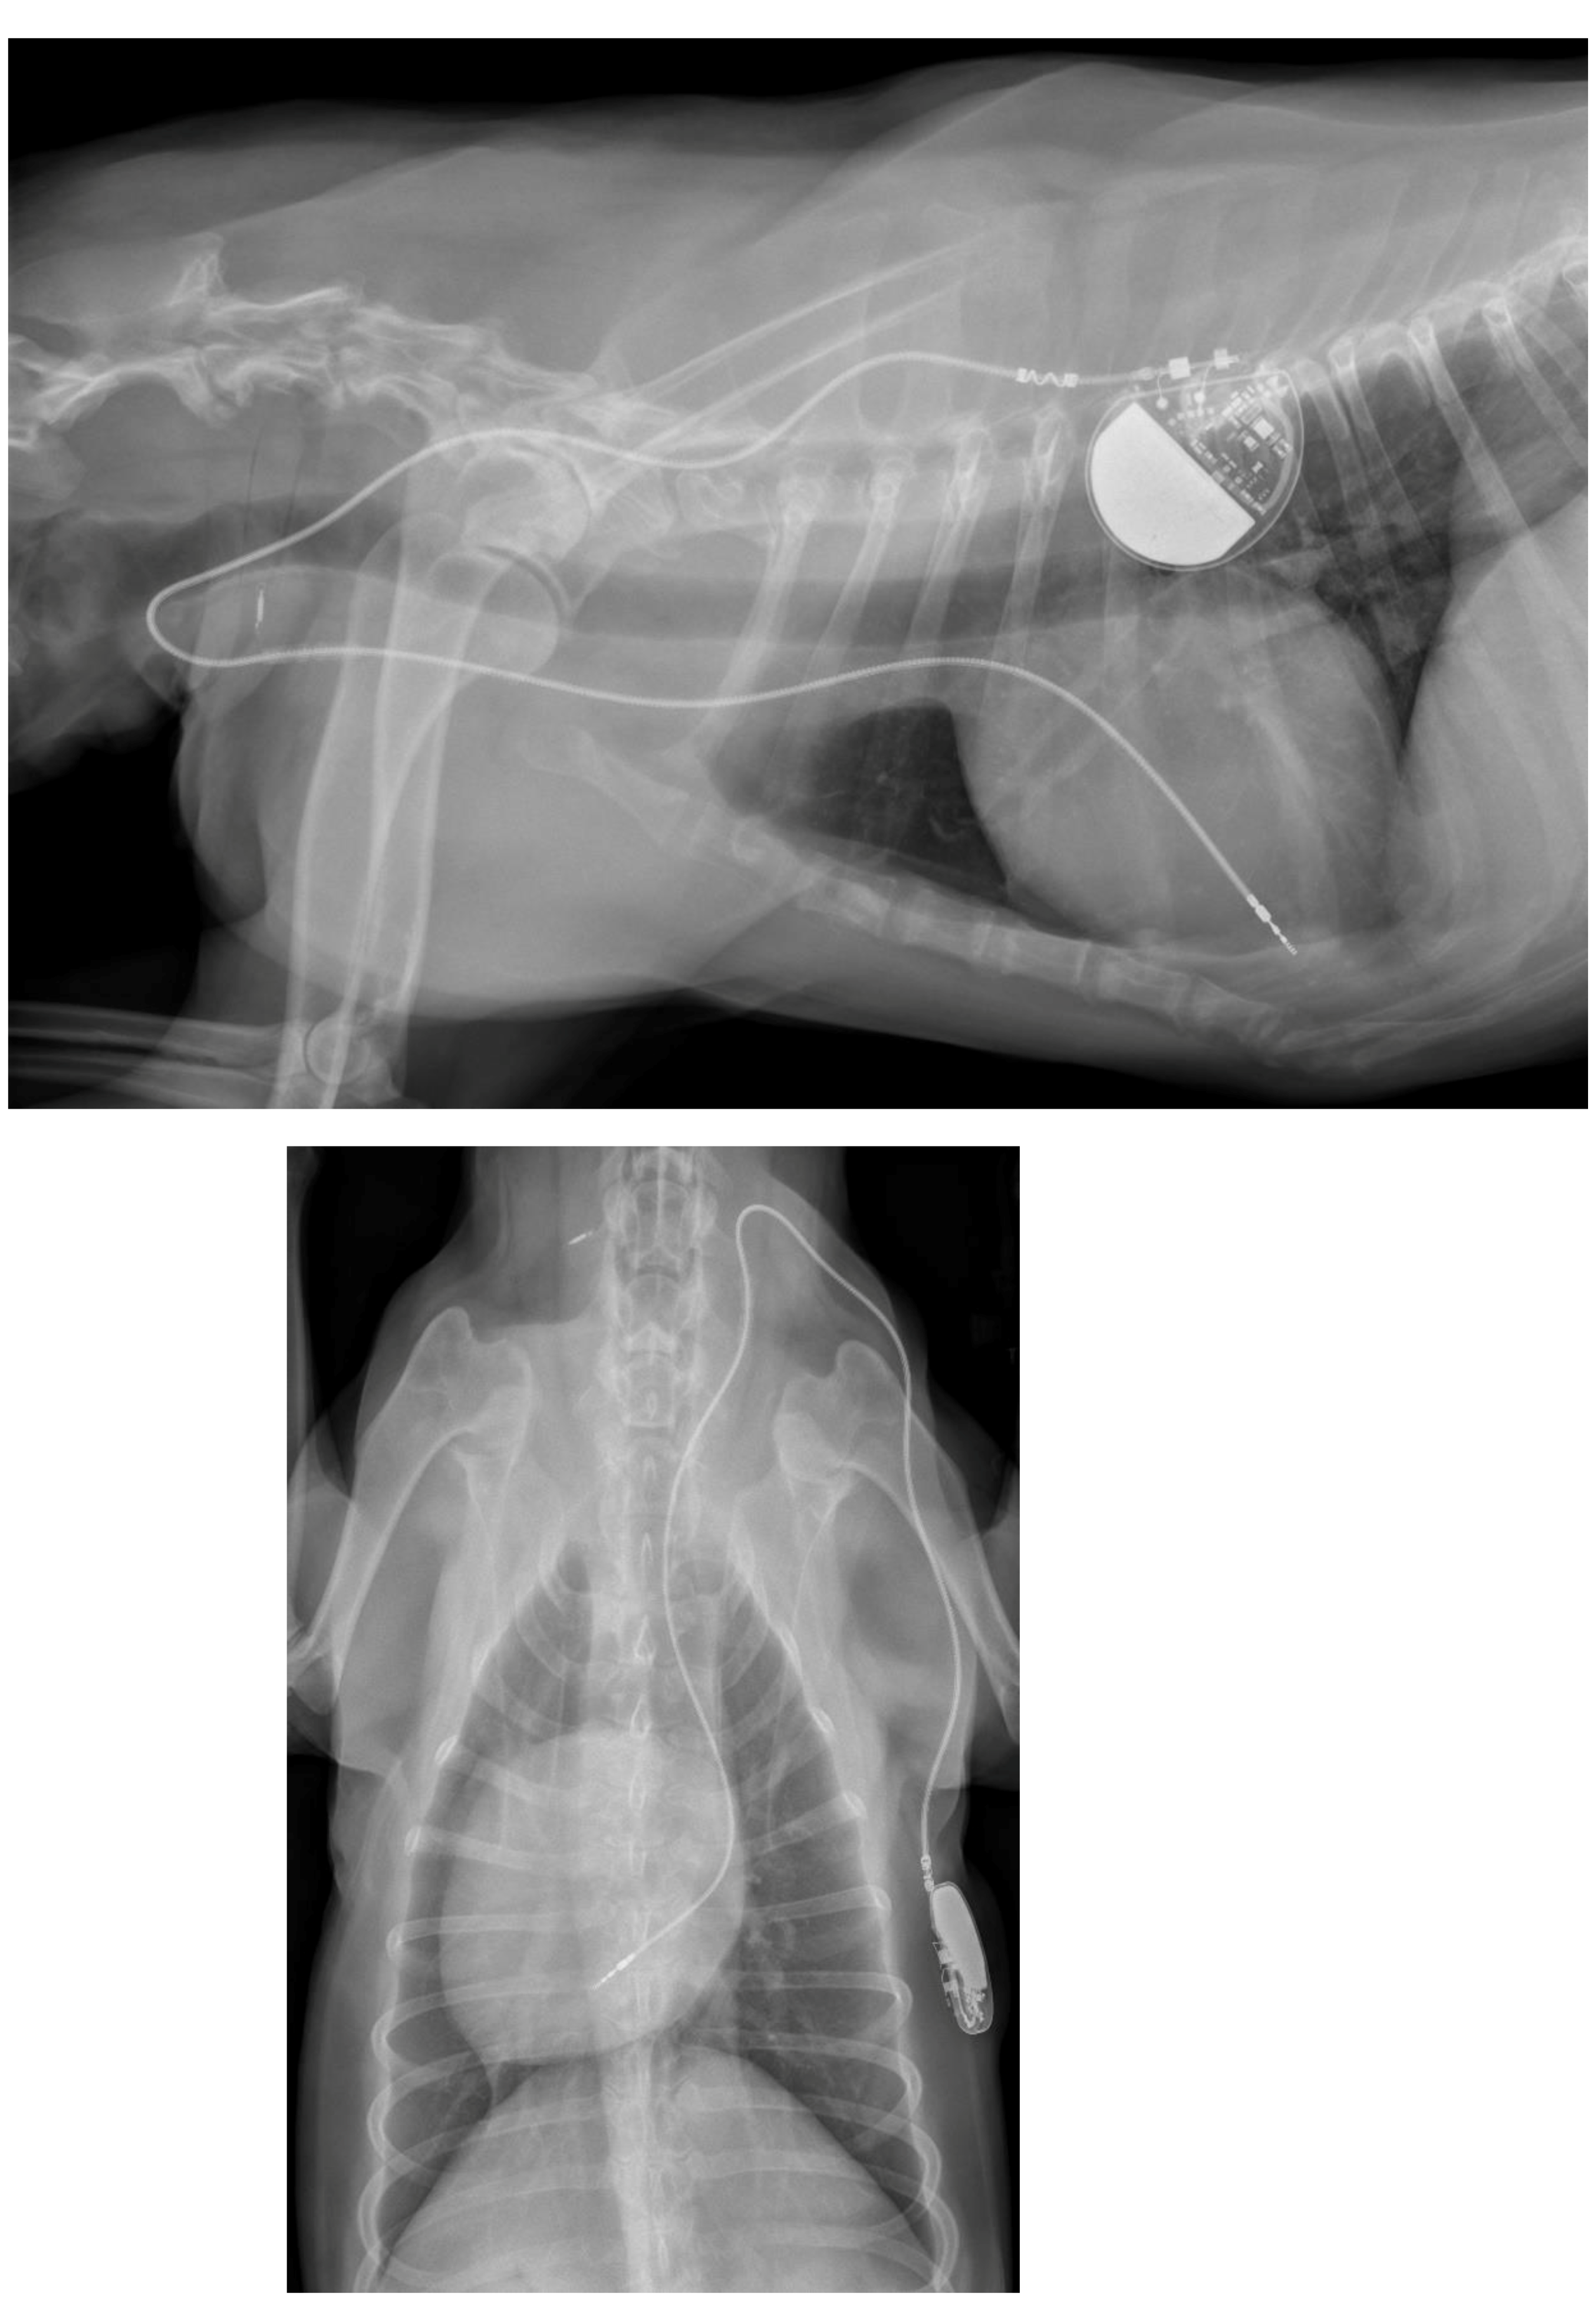

A week later, a permanent pacemaker was implanted at the authors’ teaching hospital. General anesthesia was induced with the dog in left lateral recumbency, after placement a temporary pacemaker in the conscious dog via the right saphenous vein into the right ventricular lumen, using a 4 French introducer and a 4 French temporary pacing lead under fluoroscopic guidance. The skin on the right neck and thorax between the chin and the last rib, and between the dorsal and the ventral midline were clipped, and subsequently washed with an antiseptic shampoo containing 4% chlorhexidine gluconate (Hibiscrub, Mölnlycke Health Care, Gothenburg, Sweden). Afterwards, the washed area was sprayed twice with an antiseptic solution containing 0.5% chlorhexidine gluconate and 70% isopropyl alcohol (Hibisol, Mölnlycke Health Care, Gothenburg, Sweden). A surgical skin incision was made and a transvenous permanent pacing lead with active fixation mechanism (58 cm, Capsurefix MRI Surescan 5086, Medtronic, Minneapolis, MN, USA) was implanted through the right jugular vein into the right ventricular apex under fluoroscopic guidance. A second skin incision was made on the right dorsal thoracic wall to create a pocket for the pulse generator. The free end of the pacing lead was subcutaneously tunneled from the cervical incision and connected to the pulse generator (T20 SR, Vitatron, Maastricht, the Netherlands), which was placed dorsally on the right thoracic wall under the cutaneous trunci muscle. The pacemaker was programmed for ventricular bipolar pacing and bipolar sensing in rate responsive mode (VVIR) with a variable frequency between 80–120 beats/minute with a minimum night frequency of 60 beats per minute. At implantation, the stimulation threshold was 0.25 V at 0.40 ms and the lead impedance was 750 Ohm. The pacing amplitude was set at 2.5 V and 0.40 ms, with a sensitivity of 2.5 mV. The pacing lead and the pulse generator were secured to the underlying tissue using non-absorbable multifilament suture material (Ethibond 2-0). The surgical wounds were closed with single interrupted sutures using monofilament suture material in two layers (Monocryl 3-0 for the subcutis and Ethilon 3-0 for the skin). A moisture vapor permeable spray dressing containing acrylic polymer in solvent and propellant mixture (Opsite, Smith and Nephew, Watford, England) was used to cover the two surgical wounds for preventing post-operative surgical site infection. At completion of the implantation procedure, the temporary pacemaker was switched off and the temporary pacing electrode was removed under fluoroscopic guidance. After removal of the introducer from the right saphenous vein, the puncture site was covered with a pressure bandage for 30 min. Postoperative thoracic radiographs were made to document the position of the pacing lead (Figure 3).

Figure 3. Postoperative thoracic radiographs, lateral and dorso-ventral positions, show appropriate placement of the pacing lead.